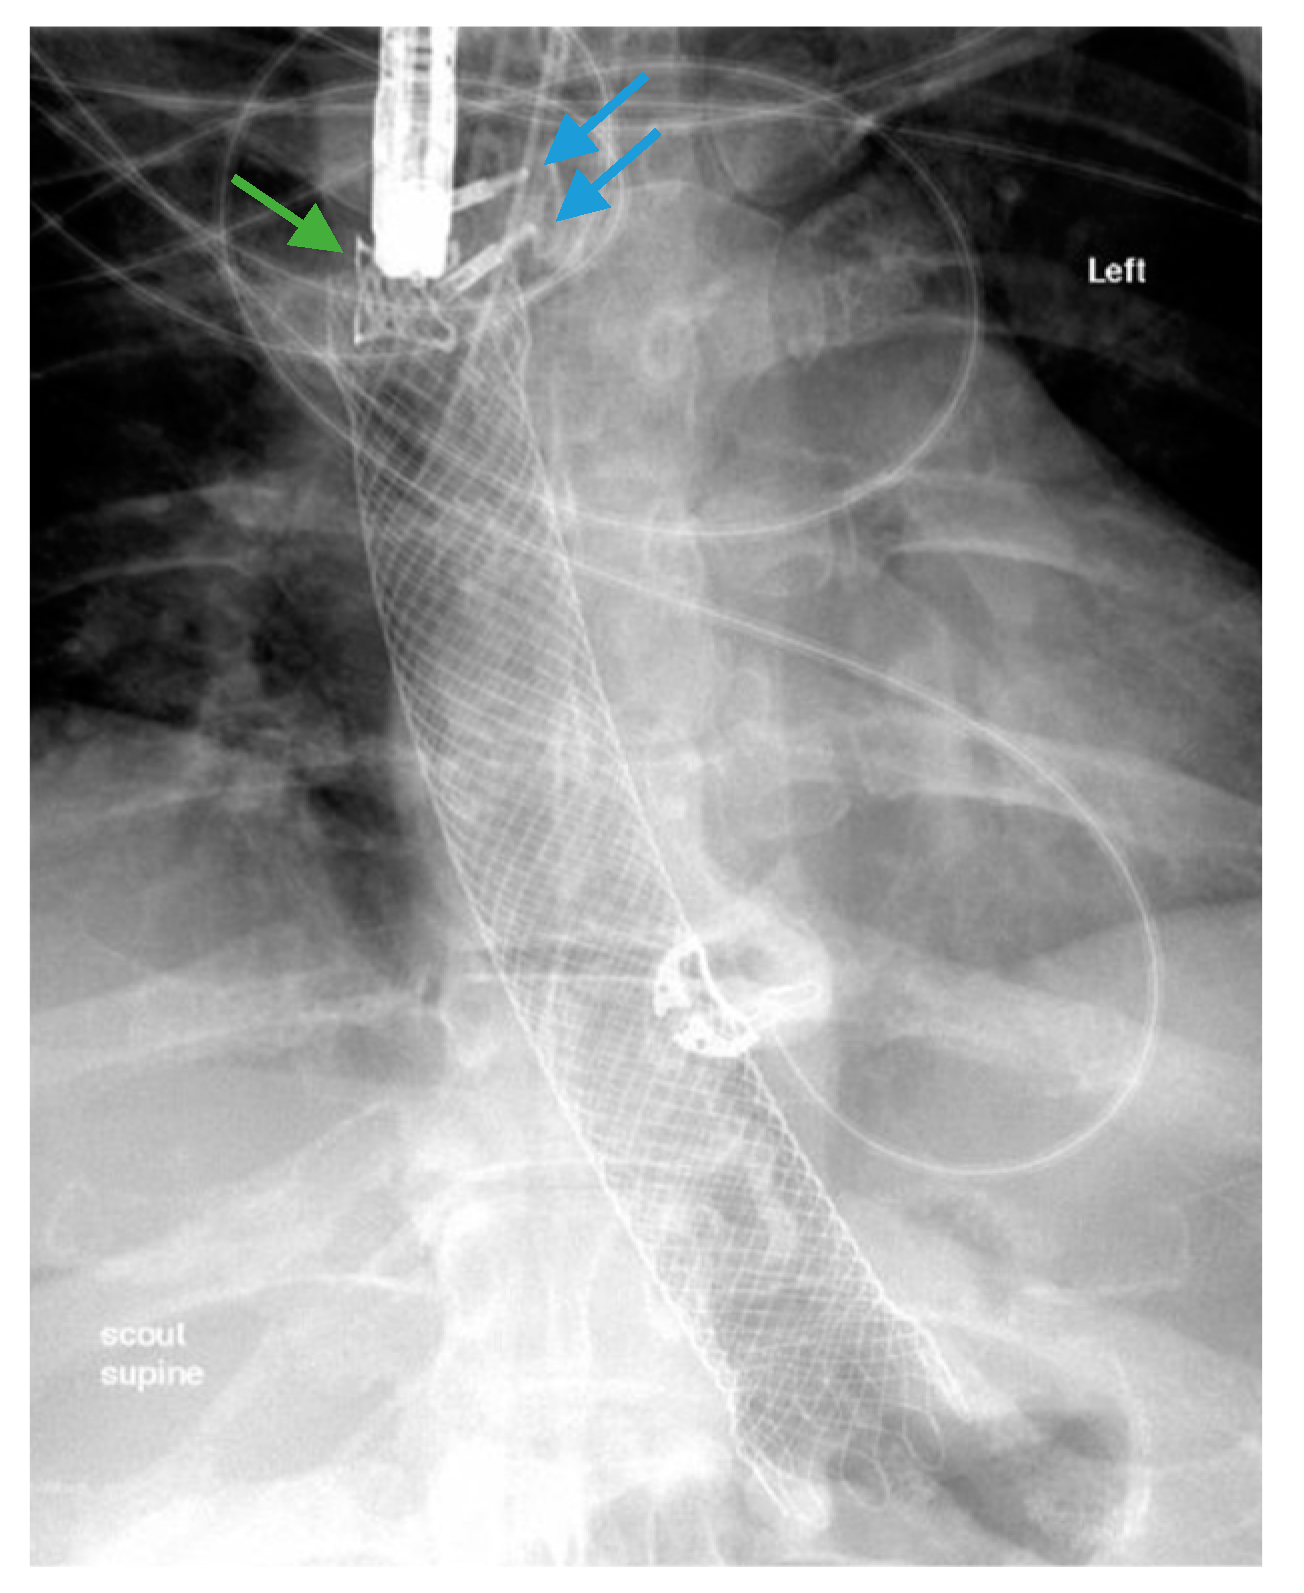

Scheme 4.

Fluoroscopic image demonstrates the placement of a 23 mm × 15 cm partially-covered esophageal self-expanding metal stent from the distal esophagus to the pylorus (arrow, top left) for the treatment of a leak in a patient following sleeve gastrectomy. Contrast injected endoscopically (arrows, top right and middle left) reveals a small, persistent sleeve leak. The endoscopic removal of the stent was subsequently attempted using a grasper (arrows, middle right and bottom left), but the stent removal was unsuccessful due to tissue ingrowth. A 23 mm × 15 cm, fully-covered, esophageal self-expanding metal stent was placed within the prior stent (arrow, bottom right) to facilitate removal after pressure necrosis of the ingrown tissue.